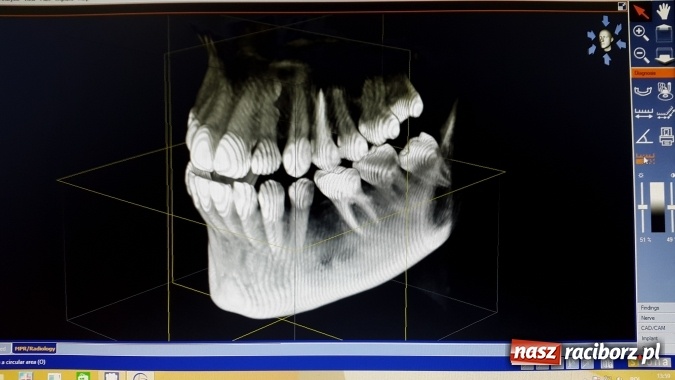

Tomograf 3D umożliwia wykonywanie zdjęć o wyjątkowo dużym polu obrazowania (prawie cała twarzoczaszka), co umożliwia uzyskanie maksymalnej ilości informacji poprzez wykonanie tylko jednego zdjęcia. Diagnostyka staje się bardzo precyzyjna. Zdjęcie w trójwymiarze dostarcza także wiele informacji na temat m.in. stawów skroniowo-żuchwowych i zatok, co umożliwia postawienie diagnozy w stadium zaawansowania choroby niewykrywalnym w innym badaniu.

Co więcej, zdjęcie takie pozwala dostrzec szczegóły niemożliwe do zobrazowania na klasycznym zdjęciu pantomograficznym w projekcji 2D. Jest to jedyne badanie ukazujące zarówno tkanki miękkie, jak twarde. Tomografia 3D to najnowszy wymiar diagnostyki, który znalazł zastosowanie w endodoncji, ortodoncji, chirurgii i implantologii. Zaletą tej metody jest możliwość dokładnej lokalizacji zębów zatrzymanych oraz innych zmian chorobowych, a także odszukanie dodatkowych kanałów podczas leczenia kanałowego, co często bywa niemożliwe w oparciu o zdjęcia 2D.

Diagnostyka ortodontyczna także stała się prostsza i dokładniejsza, bowiem wykorzystanie wielu projekcji na zdjęciu 3D pozwala na precyzyjne planowanie leczenia, a także kontrolę jego przebiegu. Dziedziną stomatologii, w której tomografia 3D znalazła najszersze zastosowanie jest implantologia. Zdjęcia takie są niezastąpione przy ocenie ilości kości, położenia kluczowych struktur anatomicznych (np. dno zatok szczękowych, przebieg kanałów nerwów), a także przeprowadzeniu symulacji implantacji. Pozwala więc bezbłędnie zakwalifikować pacjentów do zabiegu wszczepienia implantów.